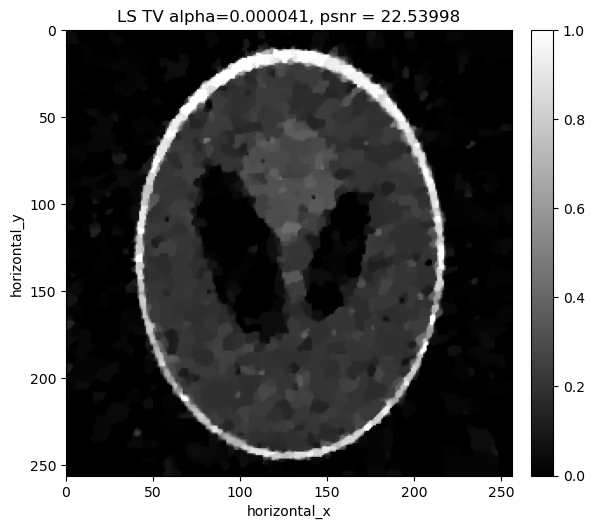

Reconstructing the noisy data using least squares with Total Variation regualrisation#

In addition to the least-square term, we considered a Total Variation Regulariser. So, for the LS-TV problem, we want to minimize the following:

\[||Y-Ax||_{2}^{2} + \alpha \, TV(x)\]

where \(\alpha\) is the regularization parameter that balances the two terms. In the next box, we search over a range of values of \(\alpha\) to find the best one for our data.

[22]:

if i%modulo == 0:

show2D([recon_ls_tv], ["LS TV alpha=%7.6f, psnr = %7.5f" % (alpha,psnr_ls_tv_alpha[i])], cmap=cmap,fix_range=(0,1), size=(10,10), origin='upper-left')

print("alpha=%7.6f, psnr= %5.3f" % (alpha,psnr_ls_tv_alpha[i]))

../../_images/demos_LS_WLS_KL_TotalVariation_34_0.png

alpha=0.000020, psnr= 17.222

alpha=0.000022, psnr= 18.315

alpha=0.000024, psnr= 19.247

alpha=0.000026, psnr= 20.028

alpha=0.000028, psnr= 20.667

../../_images/demos_LS_WLS_KL_TotalVariation_34_3.png

../../_images/demos_LS_WLS_KL_TotalVariation_34_4.png

alpha=0.000031, psnr= 21.184

alpha=0.000033, psnr= 21.600

alpha=0.000035, psnr= 21.932

alpha=0.000037, psnr= 22.192

alpha=0.000039, psnr= 22.392

../../_images/demos_LS_WLS_KL_TotalVariation_34_6.png

../../_images/demos_LS_WLS_KL_TotalVariation_34_7.png

alpha=0.000041, psnr= 22.540

alpha=0.000043, psnr= 22.644

alpha=0.000045, psnr= 22.712

alpha=0.000047, psnr= 22.752

alpha=0.000049, psnr= 22.772

../../_images/demos_LS_WLS_KL_TotalVariation_34_9.png

../../_images/demos_LS_WLS_KL_TotalVariation_34_10.png

alpha=0.000052, psnr= 22.772

alpha=0.000054, psnr= 22.756

alpha=0.000056, psnr= 22.729

alpha=0.000058, psnr= 22.694

alpha=0.000060, psnr= 22.652